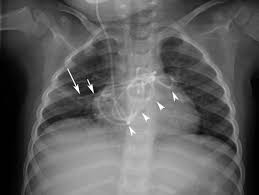

Ommaya Ventricular Access Device And Vp Shunt Radiology Case Radiopaedia Org

B Lateral Chest Radiograph Shows The Course Of The Vp Shunt Arrow Download Scientific Diagram